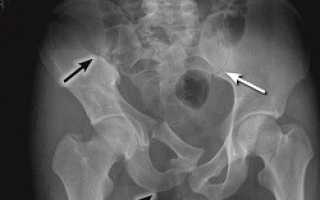

Диагноз ставится на основании:

- Рентгенография;

- Компьютерная томография.